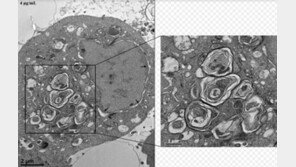

신종 코로나바이러스 감염증(코로나19) 사태로 사용이 급증하고 있는 살균·소독제의 호흡기 노출이 폐 질환을 유발할 가능성이 있다는 연구 결과가 나왔다. 24일 경희대학교 동서의학연구소 박은정 교수는 염화디데실디메틸암모늄(DDAC)에 지속적으로 노출될 경우, 체내 축적과 폐 질환 유도…